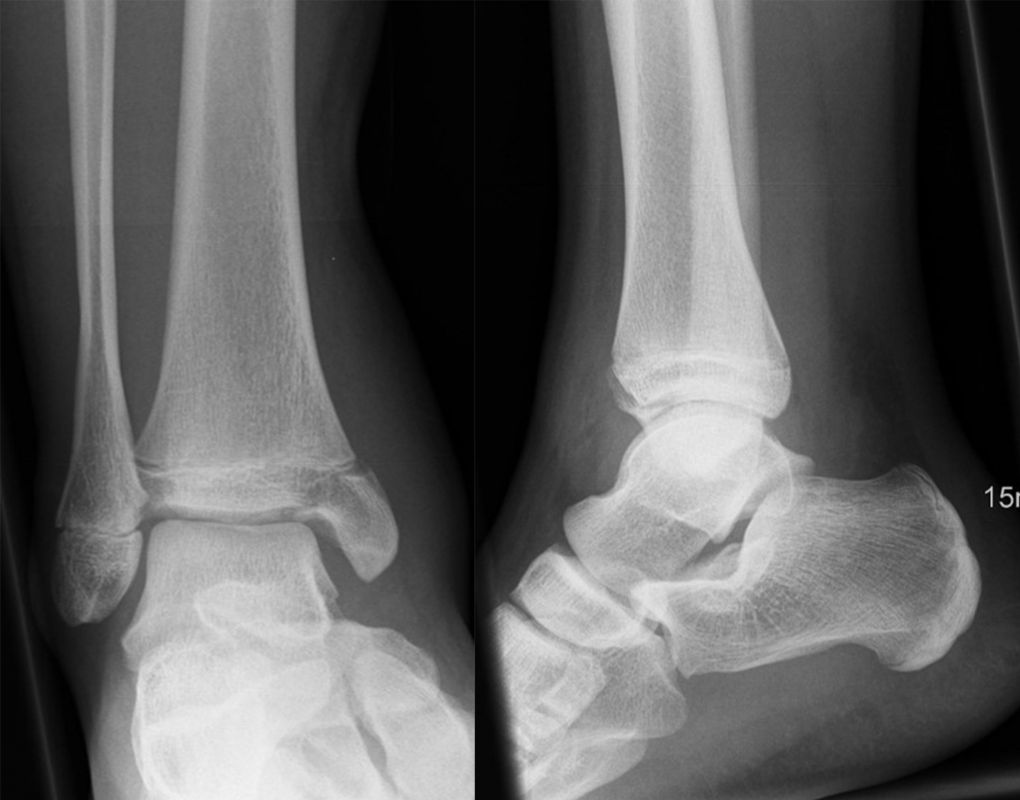

Fugengelenkfrakturen treten typischerweise vor dem 10. Lebensjahr auf, in einer Phase, in welcher die Wachstumsfugen noch weit offen sind. Dieser Frakturtyp betrifft fast ausschließlich den medialen Malleolus. Laterale Frakturen sind extrem selten, teilweise kommt es zu lateralen Bandverletzungen oder Fugenschaftfrakturen der distalen Fibula. Die Frakturlinie verläuft in einer Verlängerungslinie von der medialen Taluskante nach proximal. Häufig stellen sich Verletzungen des Innenknöchels im Röntgenbild schlechter dar, insbesondere wenn die Aufnahmen verdreht sind oder die Ebene der Fraktur bei geringer Dislokation verkippt zur Röntgenebene liegt. Besteht klinisch der geringste Hinweis auf eine Verletzung des Innenknöchels, muss aufgrund der Tragweite der Verletzung durch entsprechende Aufnahmen gegebenenfalls auch Schnittbildverfahren die Verletzung sicher diagnostiziert oder ausgeschlossen werden (Abb. 15).

Fugengelenkfrakturen können die Wachstumsfuge durchkreuzen (Abbildung 16a), ohne oder nur mit minimaler Beteiligung der Fuge sehr weit medial liegen (Abbildung 16b) oder durch die Fuge auslaufen (Abbildung 16c). Relevant für die Wachstumsprognose ist weniger die Form der Fraktur, sondern das Alter des Patienten zum Zeitpunkt des Traumas sowie das Ausmaß der Schädigung der Wachstumsfuge, wobei eine Korrelation mit dem Ausmaß der Dislokation besteht.

Behandlungsziel ist die exakte Rekonstruktion der Gelenkfläche sowie die Minimierung des Risikos einer späteren Wachstumsstörung. Dislozierte Frakturen werden offen reponiert, die Osteosynthese erfolgt mit einer Kleinfragmentschraube. Finden sich viele kleine Fragmente kann eine K-Draht Osteosynthese durchgeführt werden. Wird der Innenknöchel operiert, kann bei gleichzeitiger hochgradiger lateraler Instabilität eine Rekonstruktion des lateralen Bandapparats durchgeführt werden. Fibula Frakturen stellen sich meist spontan ein, sodass hier keine zusätzliche Osteosynthese notwendig ist.